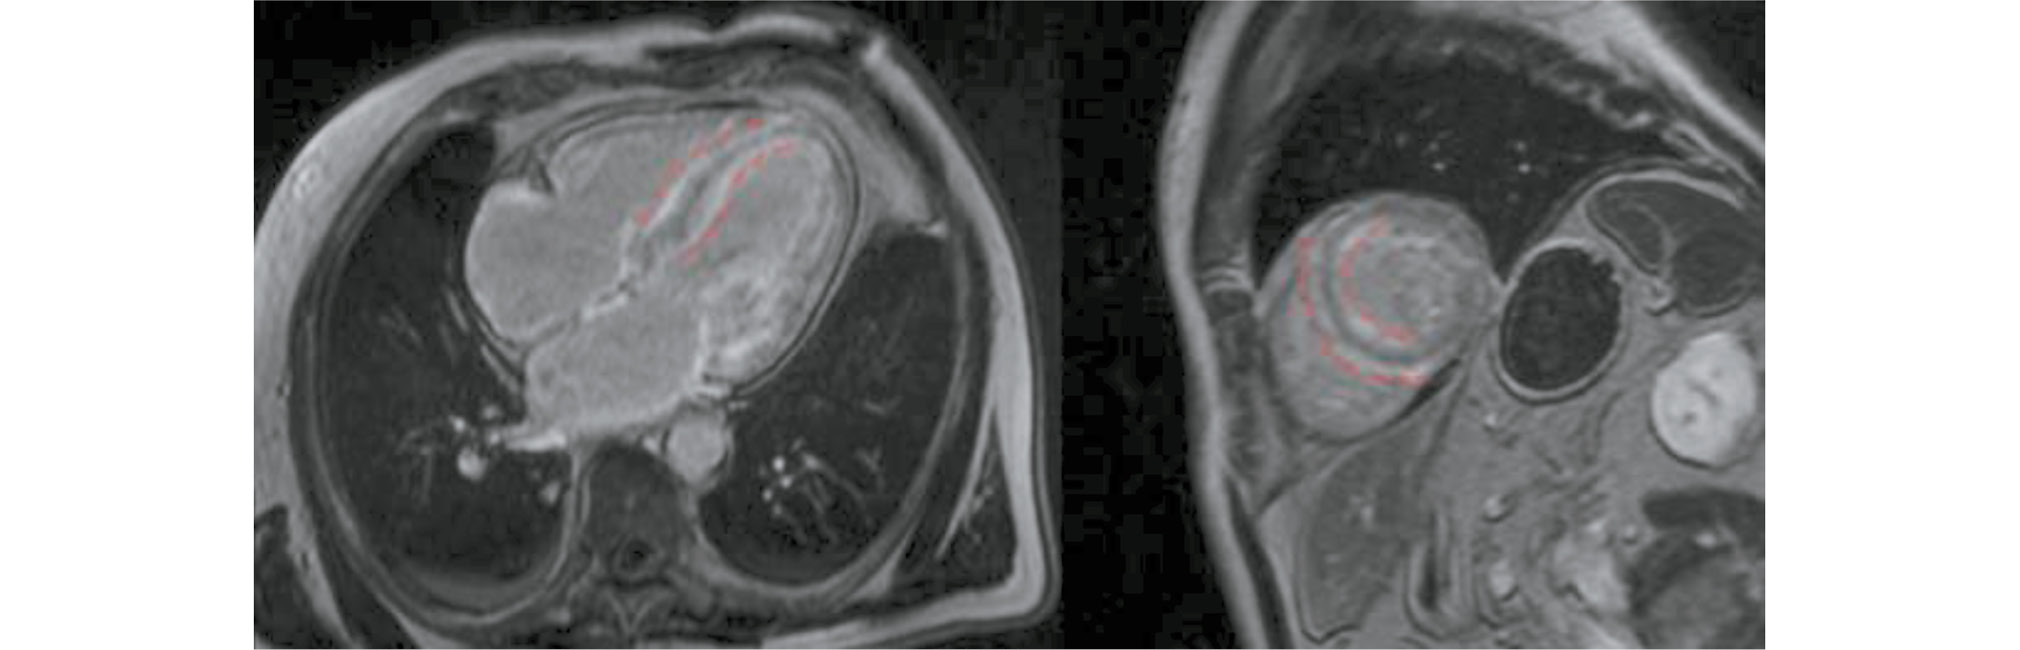

The analysis of contrast uptake distribution by cardiac segments revealed transmural LGE in Group 2 at the basal and middle levels (inferolateral segments, Fig. 4) (p < 0.05). Group 1 showed subendocardial LGE at the middle level (antero- and inferolateral segments, Fig. 5) (p < 0.05). The other segments showed no specific contrast uptake patterns (p > 0.05) (Table 3). The circular contrast uptake rates were not significantly different.

Fig. 4. Time-delayed contrast-enhanced cardiac magnetic resonance imaging scans in transthyretin amyloidosis. Transmural contrast uptake at the basal and middle levels (inferolateral segments), subendocardial contrast uptake at the basal level (anterior, anterolateral, and inferior segments) of the left ventricular myocardium (white arrows), and subendocardial contrast uptake in the interventricular septum (right ventricular involvement) (yellow arrow).